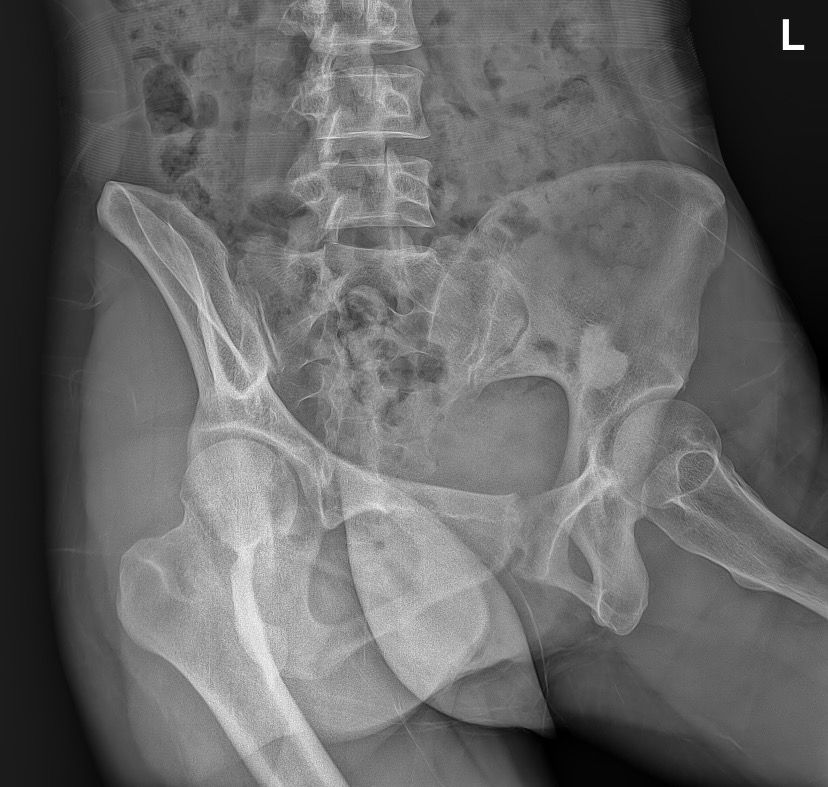

골반 x-Ray 사진 판독 좀 부탁드려요ㅜㅜ

엑스레이 찍자고 하셔서 찍었는데 왼쪽 골반뼈에 뭐가 보인다고 하시더라구요 혹인가… 하시면서 크게 신경 안쓰시는거처럼 말씀하셔서 그런가보다 하고 일단 물리치료 받고 오긴 했는데 시간이 갈수록 조금 걱정이 돼서요…

• 1번 째 사진